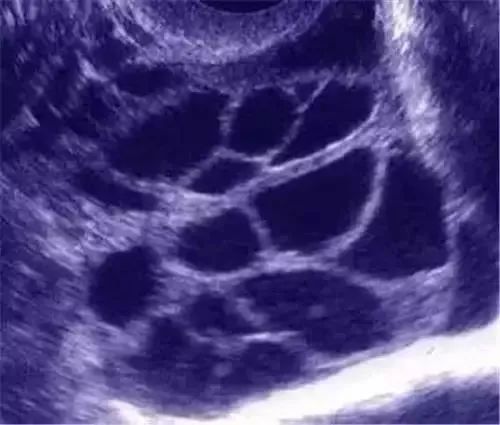

(图:B超示卵巢过度刺激声像)

除腹胀、腹部不适、恶性呕吐等症状之外,卵巢增大至5~10cm,B超提示腹水。